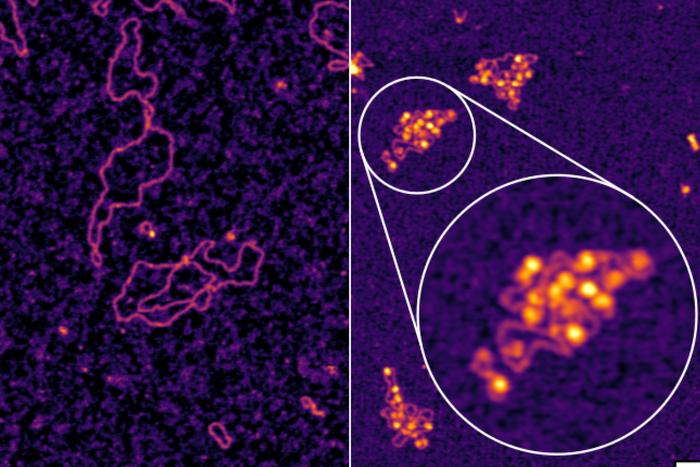

Mayo Clinic researchers have made a groundbreaking discovery in the field of ovarian cancer treatment by identifying a novel immunotherapy…